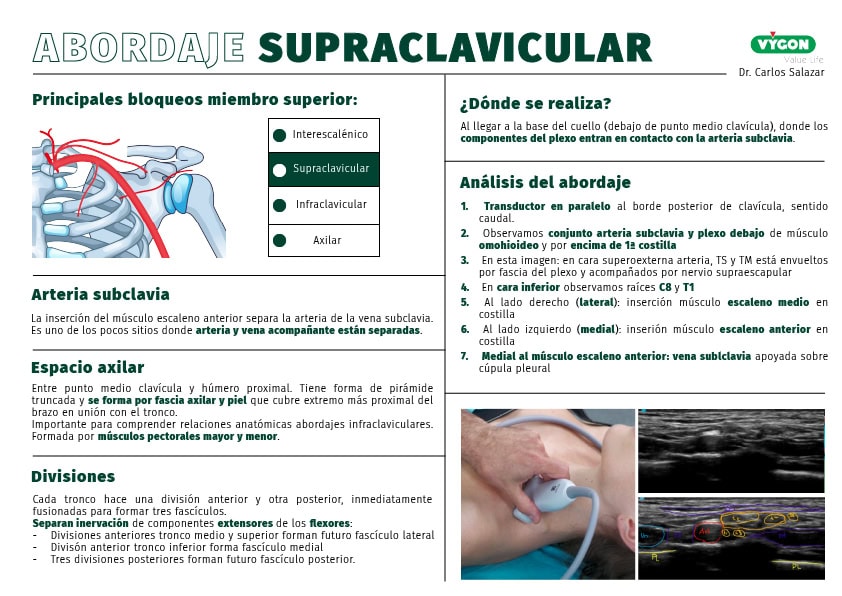

A partir de las indicaciones del abordaje supraclavicular del Dr. Carlos Salazar en su formación «Abordajes del plexo braquial, 4 bloqueos que todo anestesista debe conocer»:

En el miembro superior, existen cuatro bloqueos del plexo braquial que debemos conocer a la perfección: interescalénico, supraclavicular, axilar e infraclavicular.

Hoy profundizaremos en el abordaje supraclavicular.

¿Qué ocurre en el abordaje supraclavicular?

Al llegar a la base del cuello, por debajo del punto medio de la clavícula, todos los componentes del plexo entran en contacto con la arteria subclavia. Es en este sitio donde se realiza el abordaje supraclavicular.

Tres referencias anatómicas que debemos conocer antes de realizar el abordaje:

Arteria subclavia

La arteria subclavia asciende desde el mediastino superior por la cúpula pleural y luego cursa sobre la cara superior de la primera costilla, entre las inserciones de los músculos escalenos anterior y medio, por debajo del punto medio de la clavícula.

La inserción del músculo escaleno anterior separa la arteria de la vena subclavia y es de los pocos sitios anatómicos en los cuales una arteria y su vena acompañante se encuentran separadas.

Las divisiones

Al pasar por debajo del punto medio de la clavícula acompañando a la arteria, los tres troncos forman las divisiones.

Cada tronco hace una división anterior y otra posterior que inmediatamente se fusionan para formar tres fascículos (o troncos secundarios o cordones).

Las divisiones separan la inervación de los componentes extensores (divisiones posteriores) de los flexores (divisiones anteriores) de la extremidad superior. Más concretamente, las divisiones anteriores de los troncos superior y medio forman el futuro fascículo lateral (C5, C6, C7); la división anterior del tronco inferior forma el fascículo medial (C8 y T1); las tres diversiones posteriores forman el futuro fascículo posterior (C5-T1).

Además, la arteria subclavia, acompañando el plexo, se convertirá en arteria axilar al dejar la primera costilla por el estrecho toracocostoclavicular.

El espacio axilar

Ente el punto medio de la clavícula y el húmero proximal se localiza el espacio axilar anatómico, el cual tiene forma de pirámide truncada.

La base del espacio axilar está formada por la fascia axilar (que incluye al ligamento suspensorio de la axila) y la piel que la cubre en el extremo más proximal del brazo en su unión con el tronco.

La pared anterior del espacio axilar es importante para comprender las relaciones anatómicas de los abordajes infraclaviculares y está formada por los músculos pectorales mayor y menor.